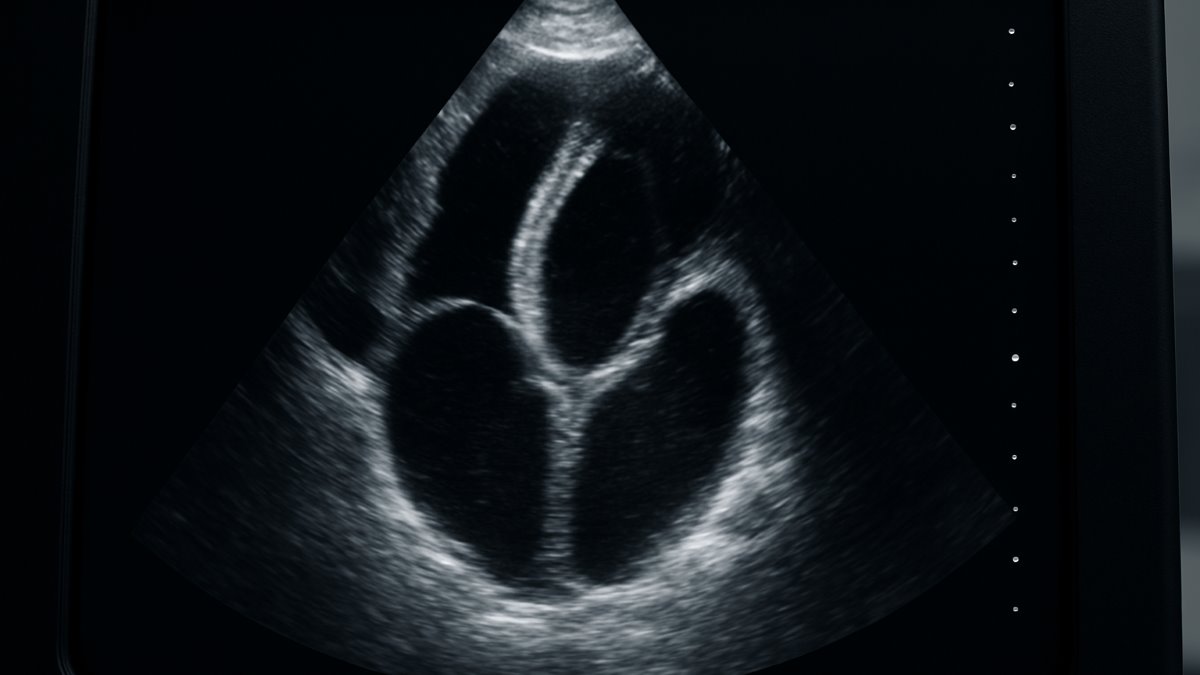

Summary: Research shows nurse support reduces heart failure readmissions, with unemployment and age also key factors. #HeartFailure #NursingCare

Background and Aims: Hospitalizations and hospital readmissions account for 75%–80% of the economic burden related to heart failure (HF). This study aims to determine the relationship between perceived social support from nurses and hospital readmission rates in HF patients and to identify potential factors associated with hospital readmission, including sociodemographic and clinical variables, perceived social support, and country. Method: We recruited 380 HF patients from two countries (Iceland 92 and Iran 288) from October 2018 to May 2020. We used the social support scale of the Family Functioning, Health, and Social Support (FAFHES) questionnaire for data collection. The hospital readmission rates were collected from patients' hospital records. We performed a general linear model (GLM) to explore the significant factors associated with readmission. Results: A total of 125 (33%) patients were readmitted within 6 months. Among them, 17% were readmitted once, 15% were readmitted twice, and 1% were readmitted three times. The strongest factor associated with the hospital readmission rate was perceived social support. Other significant factors included unemployment, age, and country of residence. Conclusion: This study underlines the important role of perceived social support in hospital readmission among HF patients. Our findings may be useful for better tailoring social support for HF patients to reduce hospital readmission. Moreover, it is recommended to investigate the effects of system-related factors, such as the strategy of healthcare systems in managing HF, on hospital readmissions. © 2025 The Author(s). Health Science Reports published by Wiley Periodicals LLC.